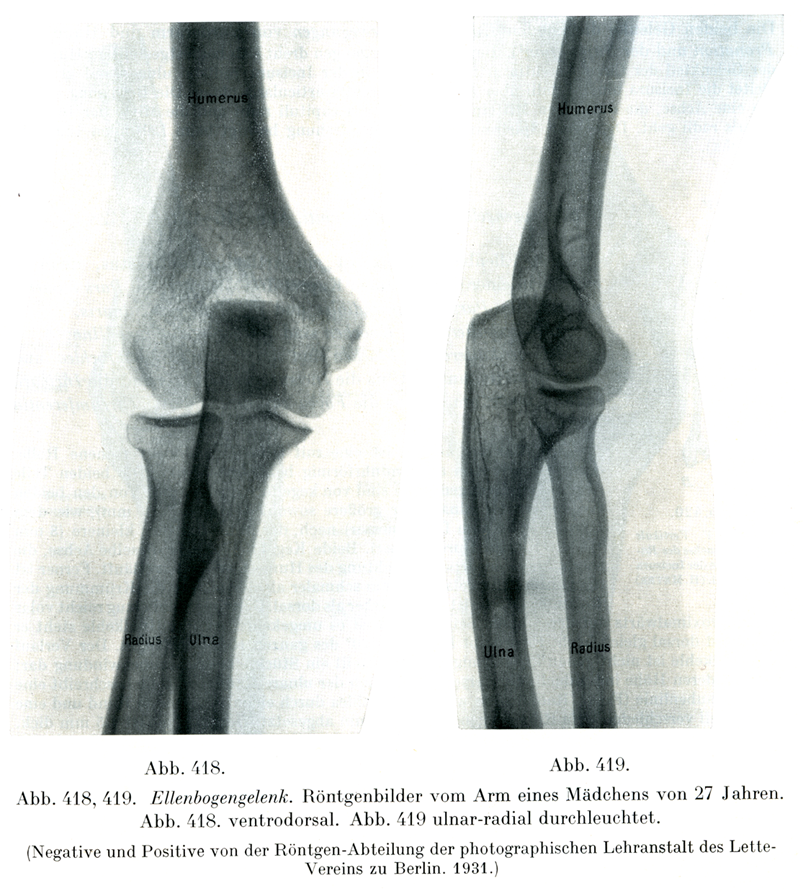

[図418, 419]肘関節27才の処女の腕のレントゲン像. 図418は掌側から背側へ照射,図419は尺側から橈側へ照射.